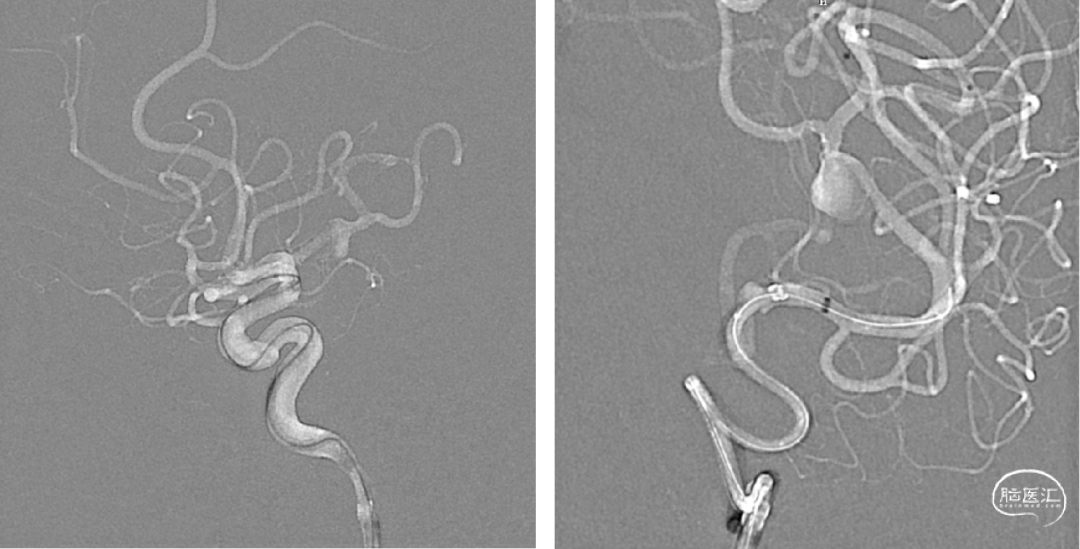

术后磁共振无脑梗及低灌注

术后半年复查,动脉瘤消失,载瘤动脉通畅